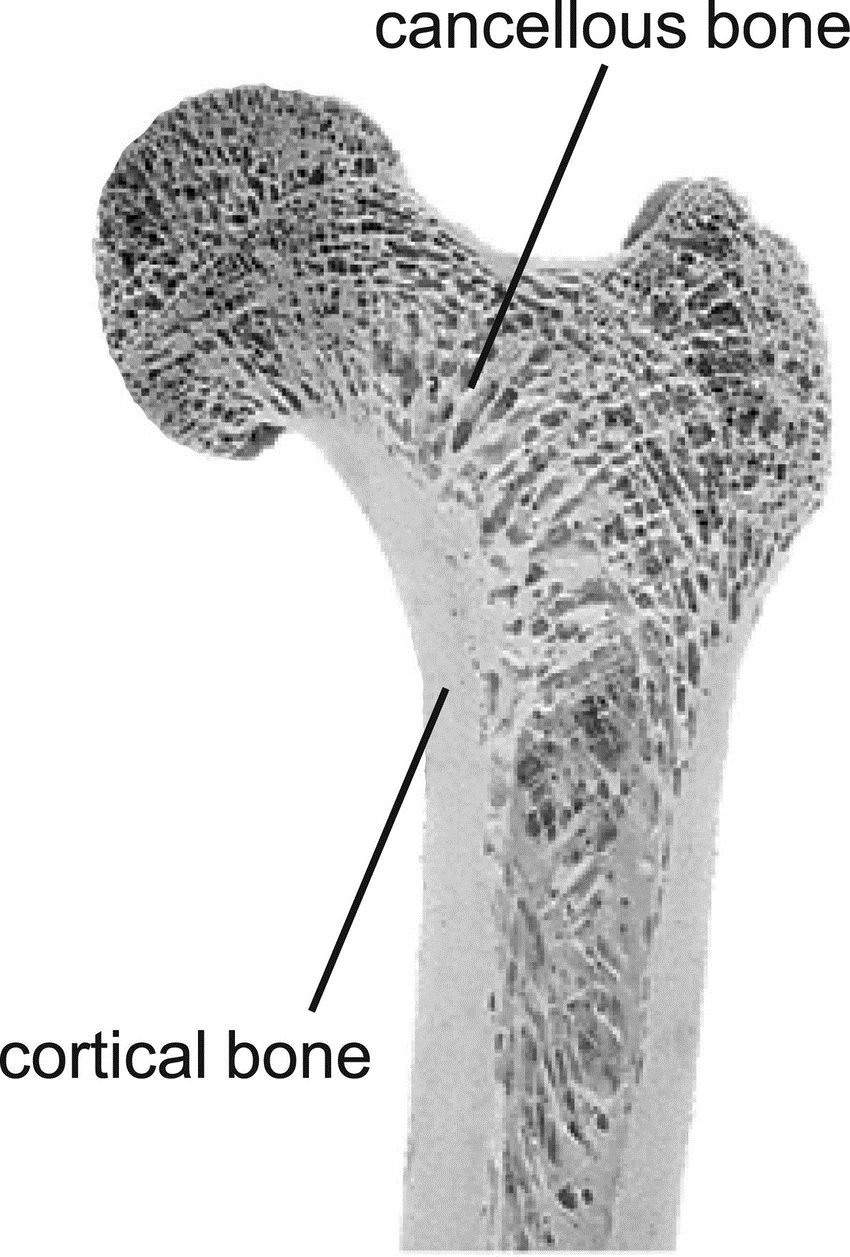

- Cancellous bone: Rich in cellular elements and highly vascular, cancellous bone grafts undergo rapid revascularization and incorporation but provide limited structural support. Common donor sites include the iliac crest, greater trochanter, proximal tibia, and in oral surgery, the mandibular ramus or symphysis (Misch, 1997).

- Cortical bone: Provides excellent structural integrity but revascularizes more slowly than cancellous bone. Cortical grafts are typically harvested from the mandibular ramus, tibial shaft, or fibula (Marx & Morales, 1988).